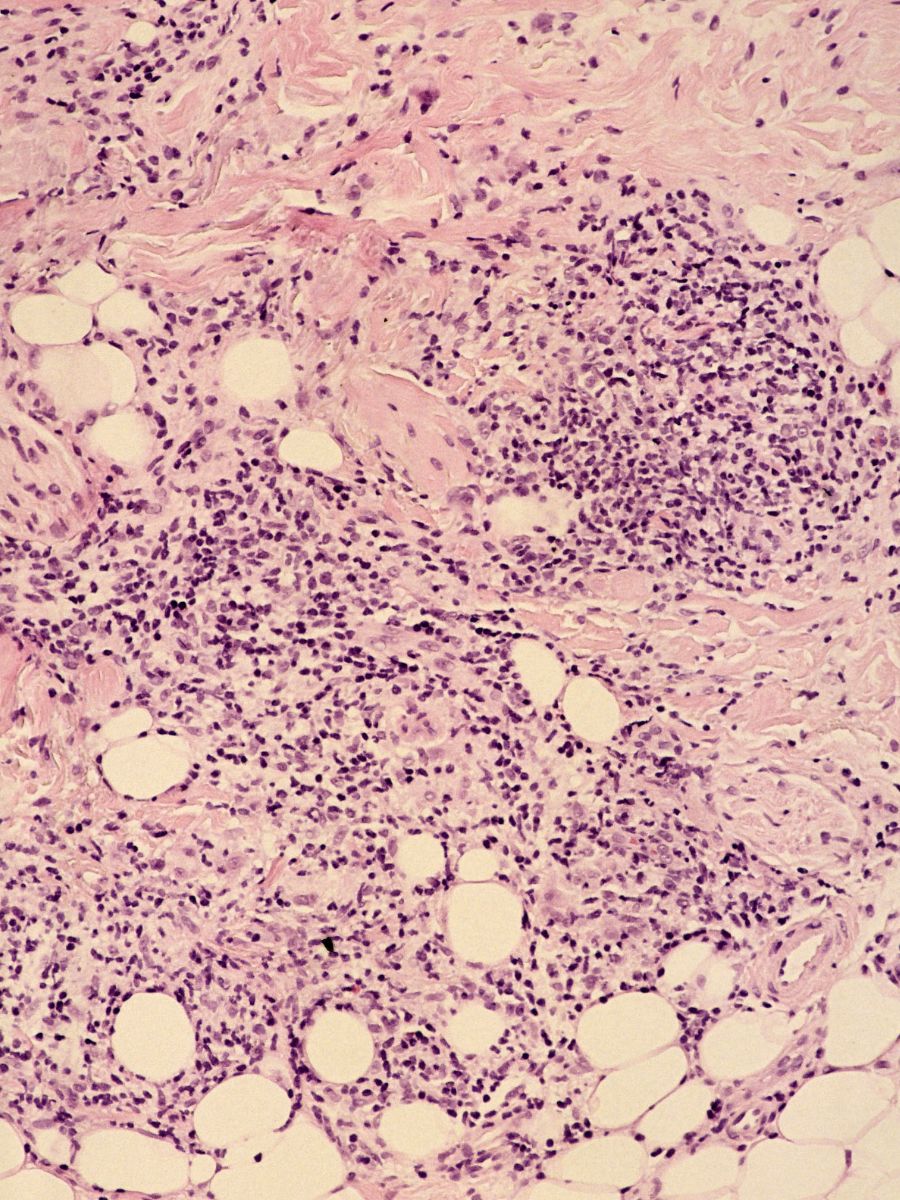

PA:- vroege stadia: oedeem en perivasculair infiltraat.

- later stadium: granuloomvorming, niet te onderscheiden van granuloomvorming

bij sarcoidosis of M.Crohn, soms soortgelijke afwijkingen in regionale lymfklieren.

![Cheilitis granulomatosa (click on photo to enlarge) [source: www.huidziekten.nl] Cheilitis granulomatosa](../../../images/cheilitis-granulomatosa-4z.jpg) |

![Cheilitis granulomatosa (click on photo to enlarge) [source: www.huidziekten.nl] Cheilitis granulomatosa](../../../images/cheilitis-granulomatosa-5z.jpg) |

![Cheilitis granulomatosa (click on photo to enlarge) [source: www.huidziekten.nl] Cheilitis granulomatosa](../../../images/cheilitis-granulomatosa-6z.jpg) |

| cheilitis

granulomatosa |

cheilitis